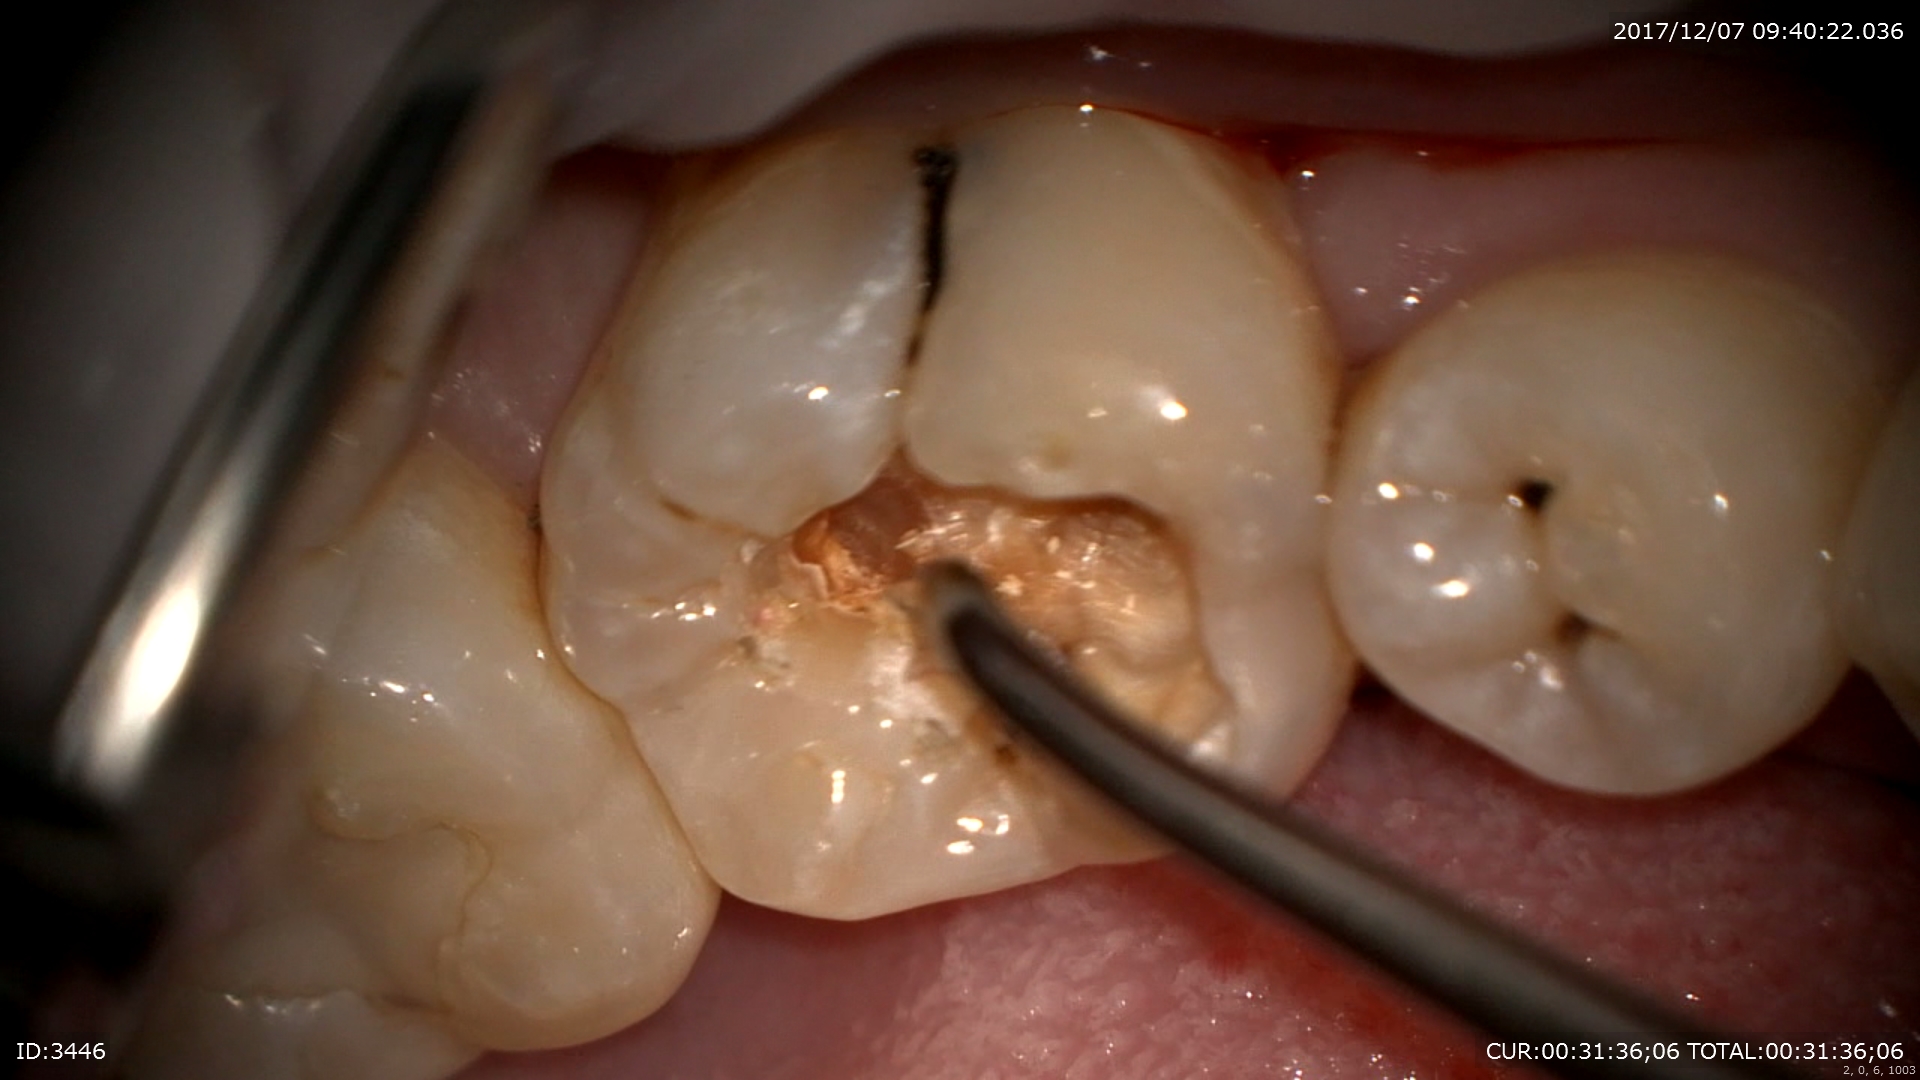

怖いのはここから。この虫歯を追従すると

ザクザク深いところまで。神経に近い。

隣の歯まで転移しています。

ほら隣の歯も。マイクロスコープですからここまで見えます。